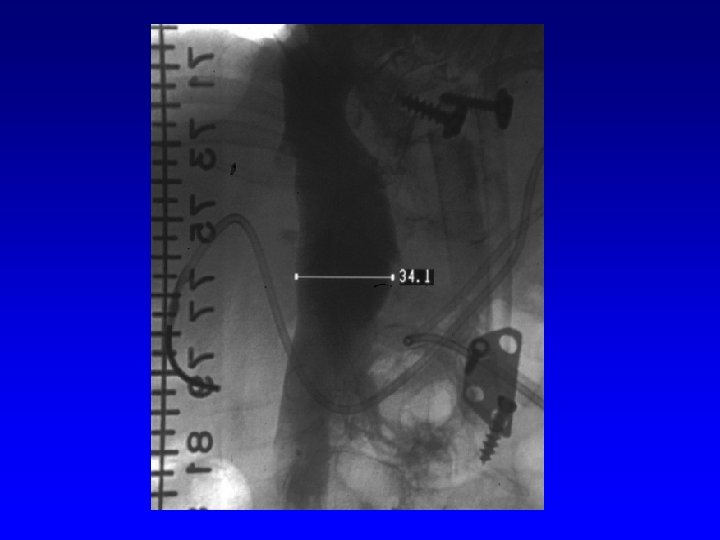

IVC Filter Removal Straight forward and Complex

Removal of an “Intravascular Foreign Body” Straight forward Loop snare Grasping device Complex Multiple devices used including angioplasty balloons, bronchoscopy forceps, and the“in situ” snare technique.

Can a Permanent IVC Filter be Removed?